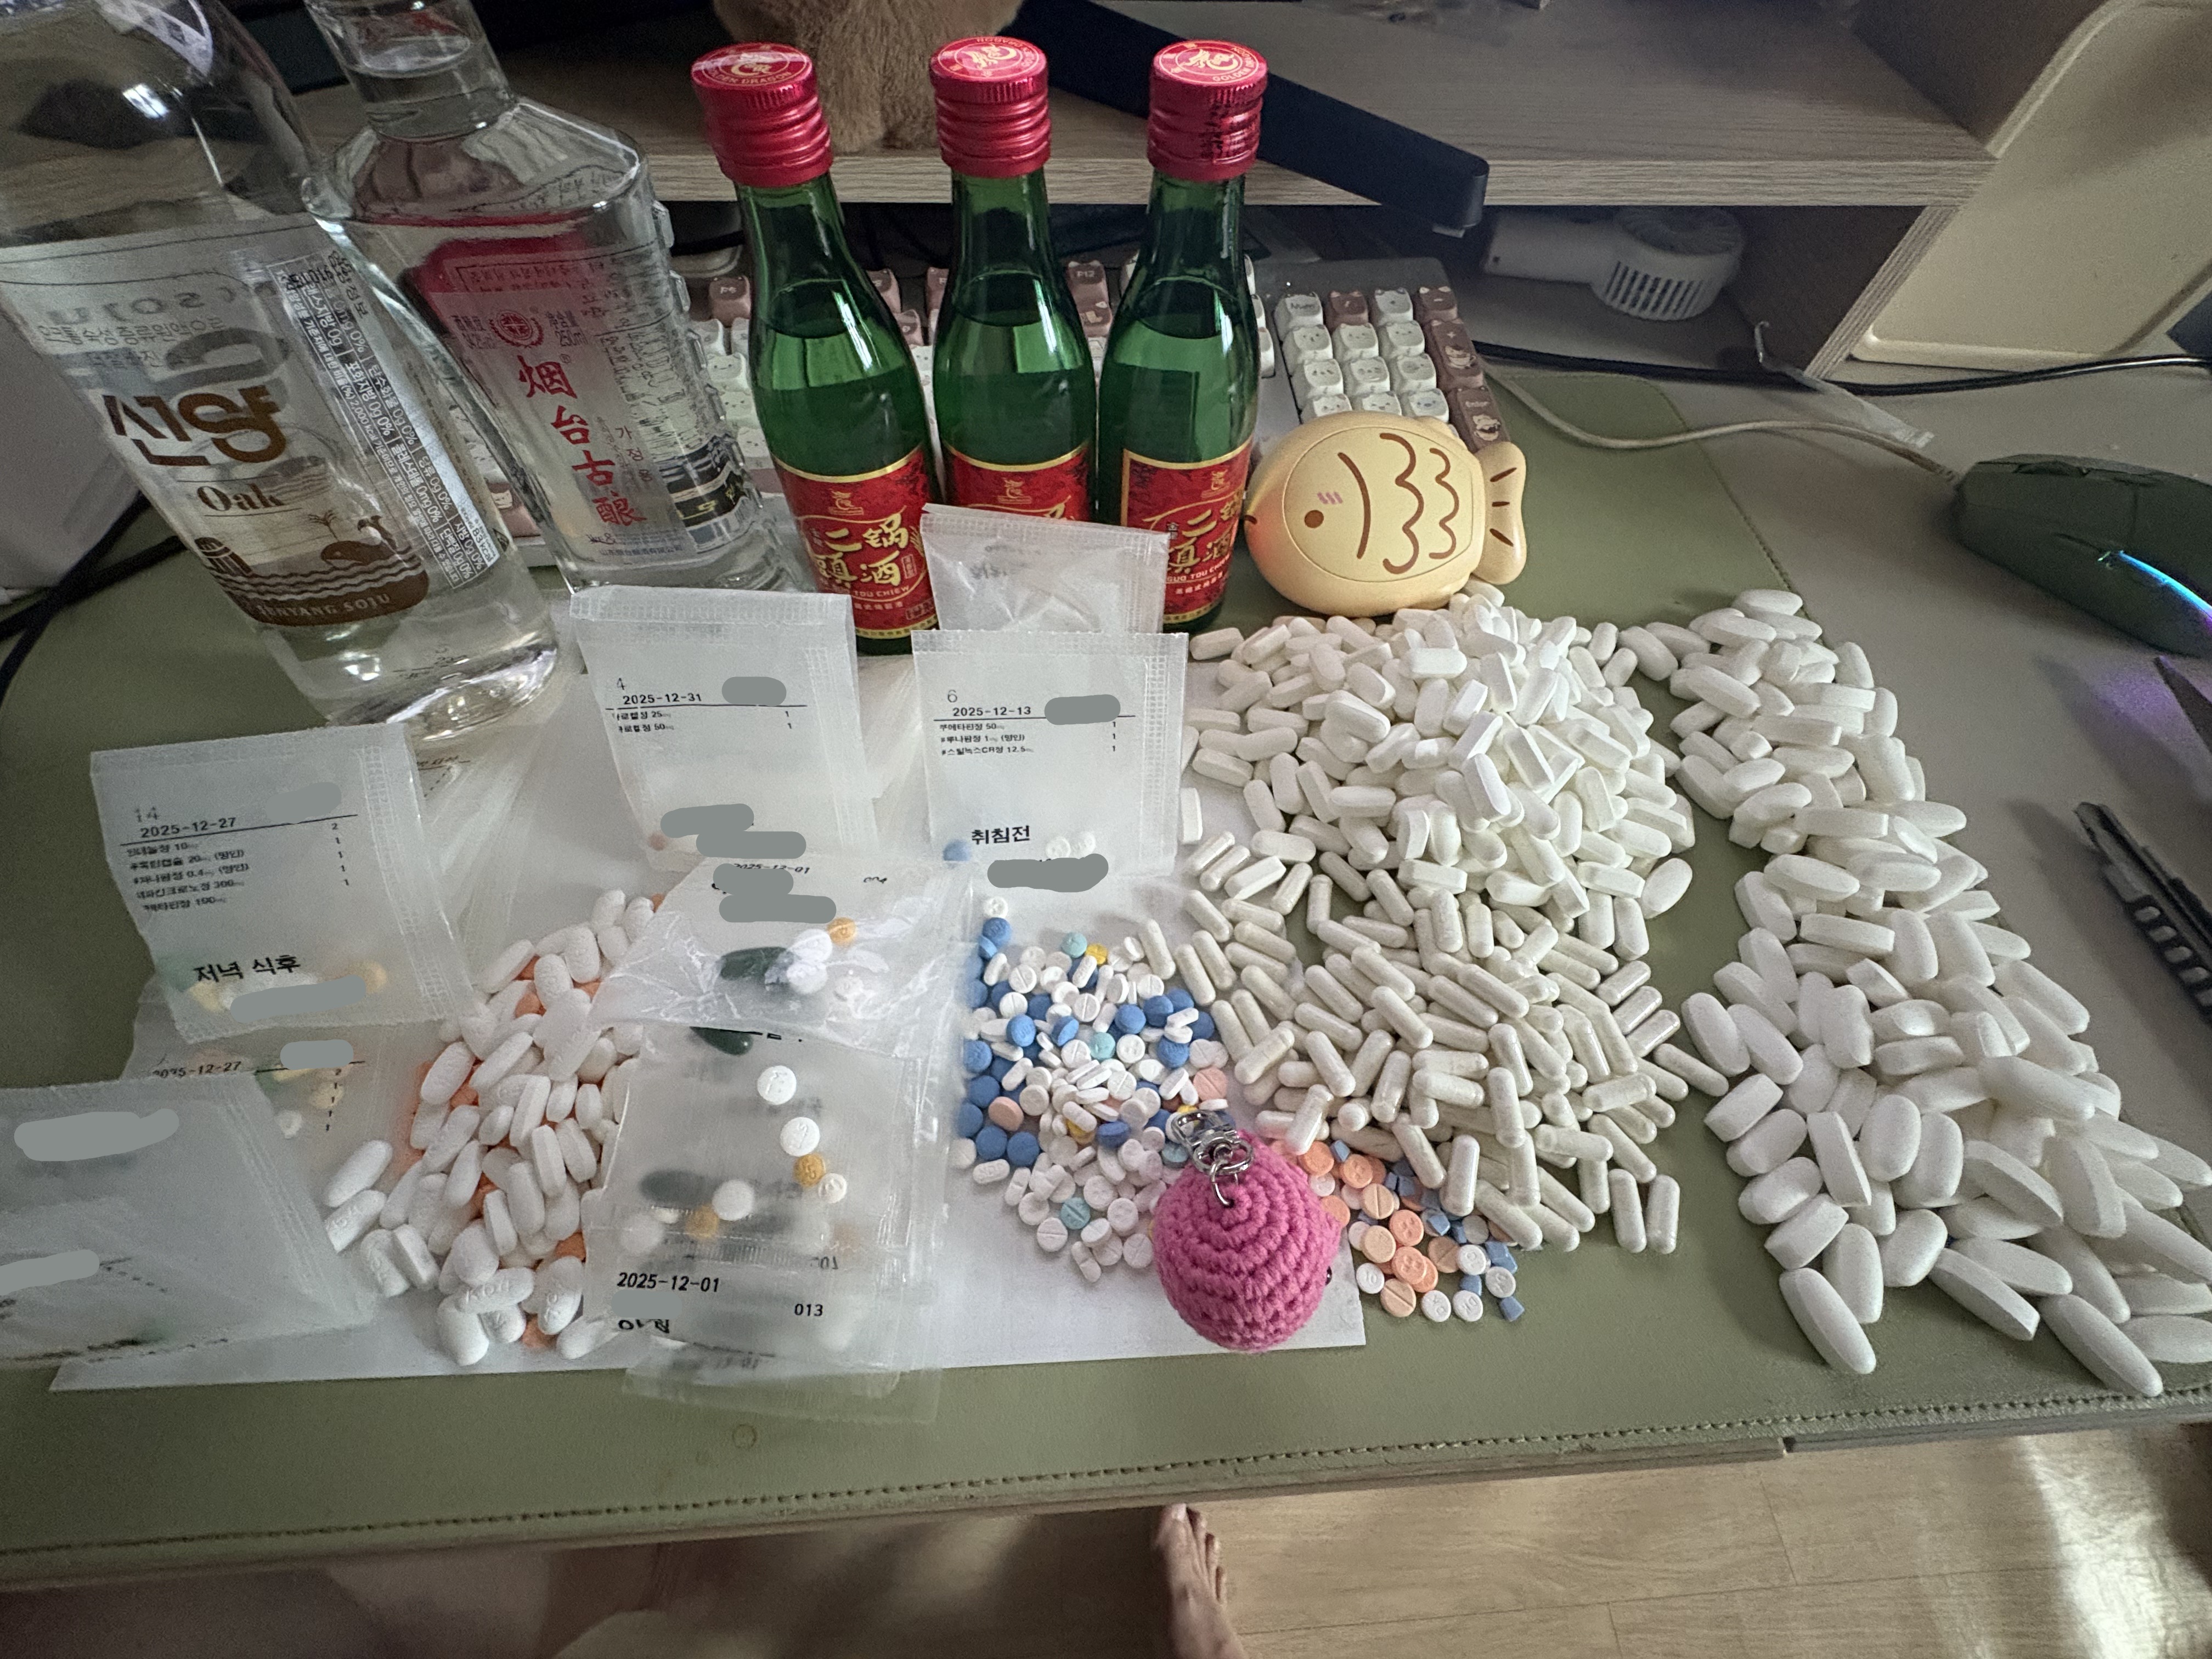

对于药物过量引起的中枢神经系统副作用,有一些不常见或常见的药物来控制症状。

评论区欢迎补充 https://t.co/7S4tGVDEM5